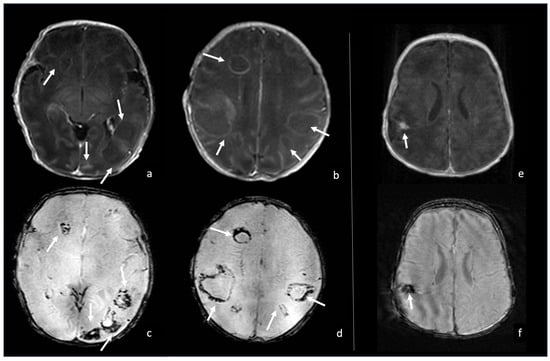

5.1. Choroid Plexitis and Ventriculitis

5.2. Meninges Involvement

5.3. Ventriculomegaly and Hydrocephalus

5.4. Effusions and Empyema